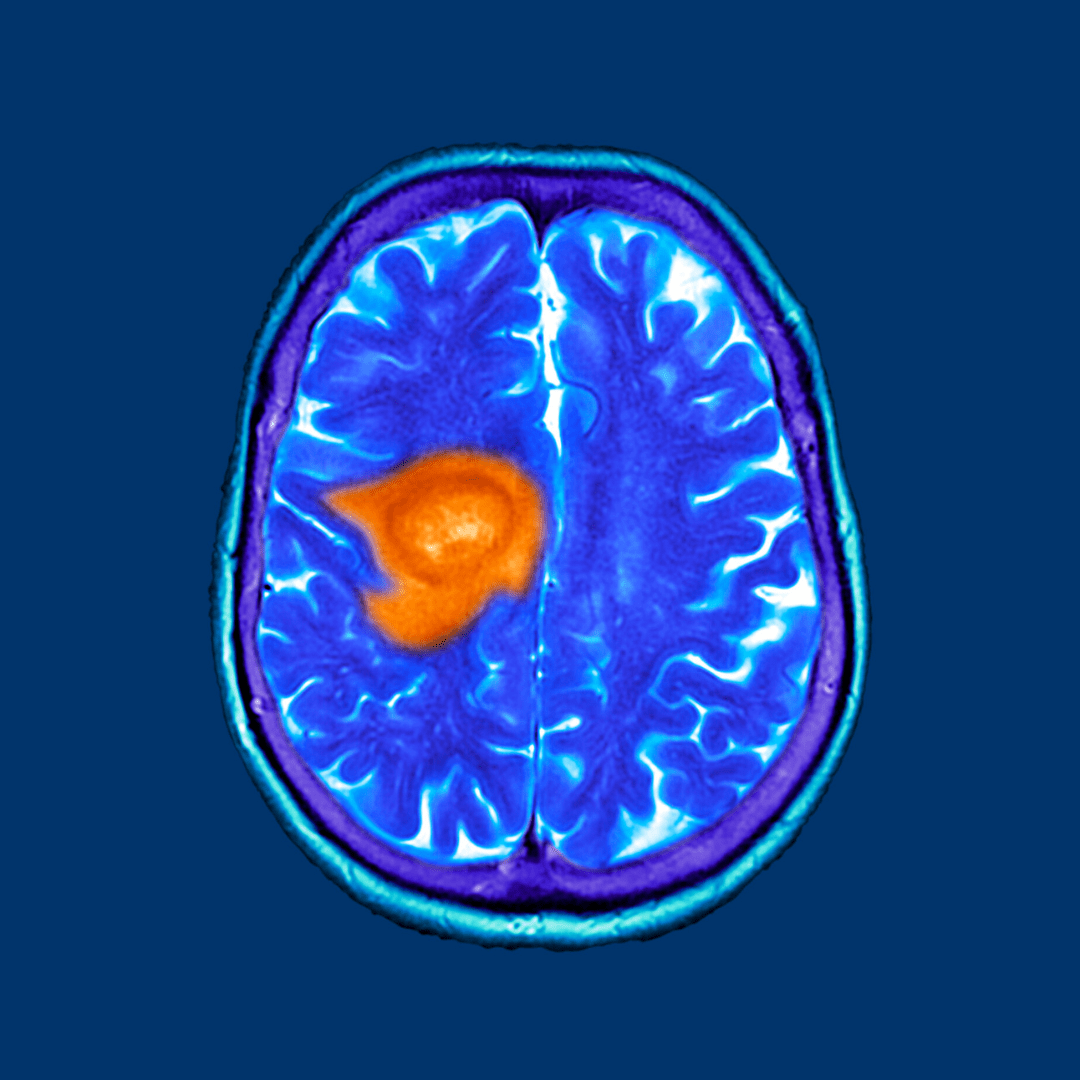

As cancer treatment evolves, complementary therapies are gaining attention for their role in improving recovery and quality of life. One such option is Hyperbaric Oxygen Treatment for Cancer, which is increasingly being used alongside traditional cancer therapies like surgery, chemotherapy, and radiation. While not a cure, this innovative approach can support healing, reduce side effects, and enhance overall well-being.

When applied as hyperbaric oxygen treatment for cancer, this therapy is primarily used to manage side effects and complications that arise from cancer treatments—not to directly kill cancer cells.